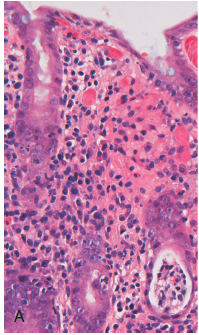

Which immune cell infiltrates predominate and where are they found?

What is the affect of Campylobacter infection on crypt architecture?